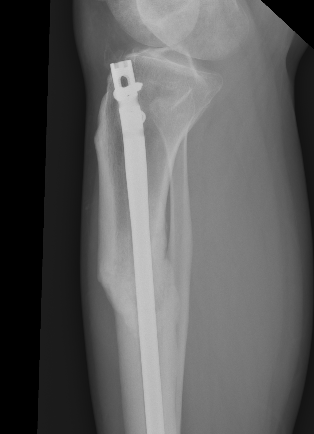

1. Change entry point

- match entry point to distal IM canal

- lateral in line with lateral tibial spine

- posterior

3. Supra-patellar approach with leg semi-extended

- flexed tibia tends to accentuate the deformity

- semi-extended reduces the deformity

- also easier to get lateral and posterior entry point